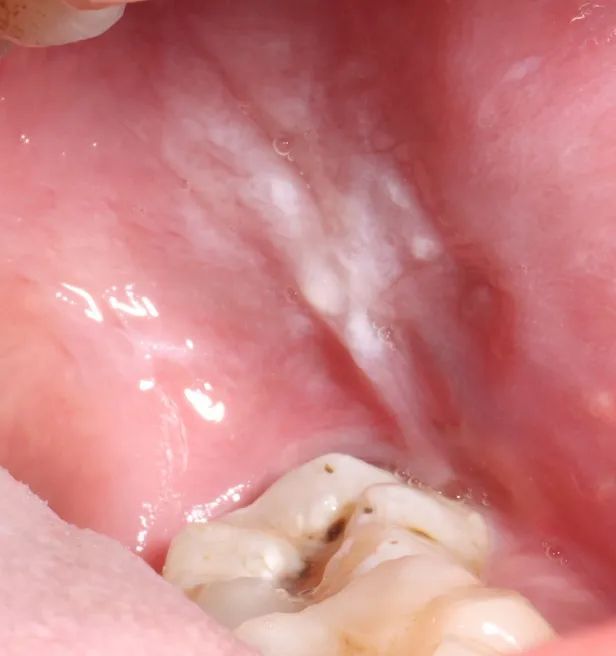

关注口腔黏膜变化,防止发生口腔癌

老年是口腔黏膜疾病高发年龄,老年人应关注口腔黏膜变化,发现口腔内有两周以上没有愈合的溃疡,口腔黏膜有硬结、白色或红色斑块等异常表现后要及时就医。

如果口腔黏膜长期受到不良刺激或有烟酒嗜好,容易发生口腔白斑甚至口腔癌。因此应早期预防,戒除烟酒嗜好,不嚼槟榔。